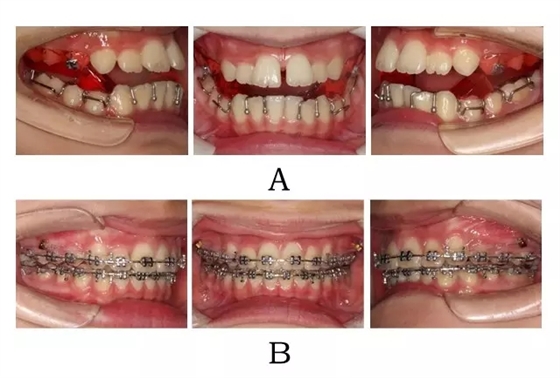

生長發(fā)育高峰期青少年,最佳方案是應(yīng)用 SGTB 矯形技術(shù),在抑制上頜的同時(shí),釋放后退的下頜向前,并引發(fā) TMJ 局部改建,鞏固由于頜位重建而取得的前牙覆合覆蓋的糾正及后牙在中性關(guān)系下的尖窩對接[9](圖3-2;3-3)。

圖3-2:頜位性突面畸形SGTB矯形及后期常規(guī)固定矯治。

(A)SGTB矯形 (B)后期固定矯治

Figure 3-2. SGTB therapy for mandibular positional prognathism. (A) SGTB orthopedics at early stage. (B) Fixed orthodontics at late stage.